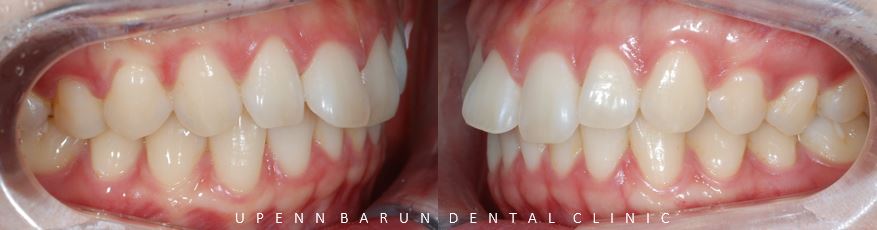

교정 전 후를 비교해보니

교정 전

윗니가 아랫니를 과도하게 덮고 있어

답답해 보였던 치아들이

교정 완료 후

과개교합이 개선되고

아랫니들이 더 잘 보이면서 시원해 보이는 느낌을 줍니다.

또한,

정중선이 일치하면서

치아들이 올바르게 배열된 모습을

확인해 보실 수 있습니다.

교정기간 23/4~24/3(11개월)